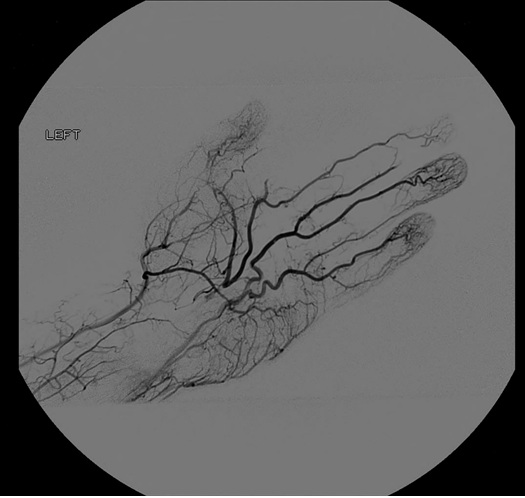

A 42-year-old male with hypertension, hyperlipidemia and smokeless tobacco use, was referred by his Primary Care Physician (PCP) to the plastic surgeon for evaluation of a cold left index finger with bluish discoloration for one year that worsened over last 4 days. The patient denied history of trauma, and had no signs of deformities or infection. Compartment syndrome and Carpal Tunnel Syndrome (CTS) were ruled out as he denied any dull aching, paresthesias, weakness or clumsiness. His hand was soft, had no swelling, non-tender, full motor function and no pain with passive movement of the digits. The left index finger was cyanotic in appearance when compared to the other digits, and cool to the touch distal to the Metacarpophalangeal (MCP) joint. Radial and ulnar artery pulses were palpable. The patient had been treated by his PCP with a calcium channel blocker with minimal improvement. Due to the acute change and likely a chronic process a vascular surgeon was consulted. Collectively the concern was ischemia of the digit so he was taken the next day to the operating room for a left upper extremity angiogram (Figure 1). In this first procedure, no interventions were performed as the diagnosis was not initially made. After careful review of the angiography he was found to have thrombosis of a PMA thus ischemia of the digit. Computed tomography angiography was performed and the PMA was identified to be thrombosed in the carpal tunnel. The next day he went to the operating room for a second procedure.

Figure 1. Type I Incomplete Superficial Palmar Arch, Coleman and Anson Classification. Angiogram findings of a patent radial artery in the wrist with one digital vessel to the thumb and forms a diminutive palmar arch to the ulnar side. The ulnar artery is widely patent into the hand and gives digital vessels to the little, ring, and long finger with only collateral contribution to the index finger and thumb. The persistent median artery is seen to be thrombosed in the hand